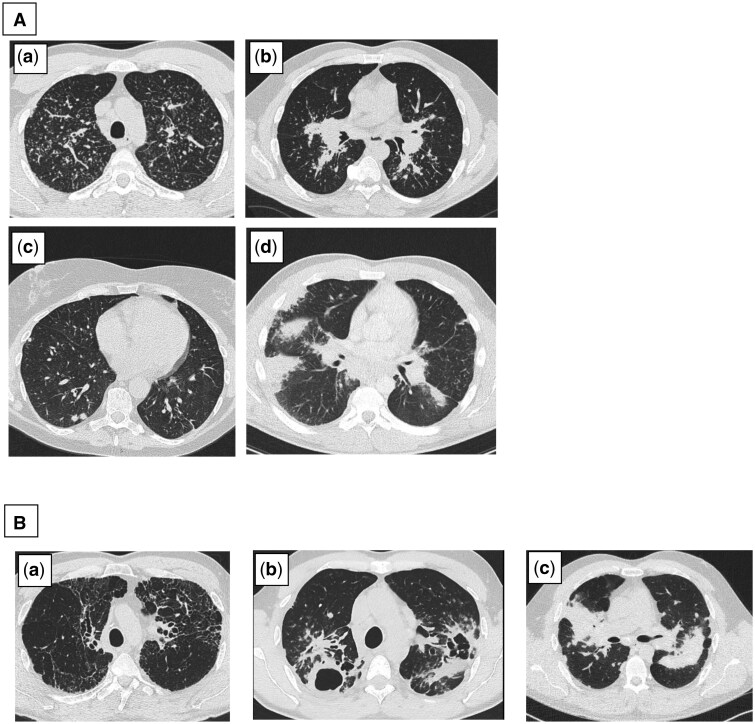

Objectives: An accurate morphological classification of distinct pulmonary phenotypes in sarcoidosis is lacking. Recently, a multinational Delphi study was conducted to reach a consensus on recognizable high-resolution computer tomography (HRCT) phenotypes in pulmonary sarcoidosis as a basis for a more distinctive classification. The reliability of these phenotypes has not yet been evaluated.

Methods: HRCT scans of adult sarcoidosis patients from the pulmonology department of a single sarcoidosis referral center were scored by three blinded independent readers. Seven phenotypes were distinguished as described in the Delphi study. They were divided into two subgroups: "non-fibrotic" and "likely-to-be fibrotic". Intra- and inter-reader reliability for scoring the predominant phenotype and the subgroup was assessed using weighted Kappa (Kw) statistics.